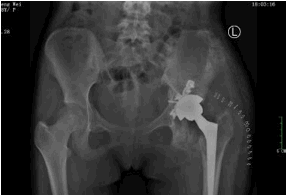

2019-07-29【南方都市报APP】车祸致骨盆多发骨折,广州医生硬核手术助18岁女孩恢复行动自如

盆骨多发性骨折,素来是骨科领域最为艰难的手术之一。但不能进行盆骨修复的伤者,尤其是女伤者,不仅可能影响到将来的分娩、生育,而且连正常的行走运动都会受限。

2019-07-29【信息时报】车祸致骨盆多发骨折,高难度手术助她恢复自如行动

来自江西赣州的18岁花季少女小彭,在一年前不幸意外遭遇车祸导致骨盆多发性骨折,当时当地医院当即为她进行了左髋臼粉碎性骨折手术治疗。